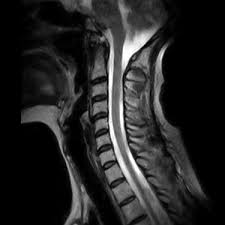

Stwardnienie Rozsiane Rezonans - Stwardnienie Rozsiane Objawy Leczenie Przyczyna Rokowania / Na podstawie przedstawionych przez panią danych tj.. Stwardnienie rozsiane (sm) a ciąża diagnostyka sm: Obecnie mr stosuje się standardowo w diagnostyce sm, pozwala na potwierdzenie rozproszenia objawów choroby w czasie i przestrzeni. Jego wykonanie dostarcza rzetelnych i dokładnych informacji, wystarczających do postawienia diagnozy lub jej wykluczenia. Głównym badaniem obrazowym, pozwalającym na wykrycie sm, jest rezonans magnetyczny głowy, mózgu oraz rdzenia kręgowego. Zdarza się jednak niekiedy, że wynik rezonansu magnetycznego nie jest jednoznaczny.

Rezonans magnetyczny pozwala na wykrycie nawet najmniejszych blaszek (płytek) i umożliwia ich odróżnienie od zmian spowodowanych obecnością guza lub uszkodzeniem naczyń krwionośnych, na przykład w wyniku urazu. Że pacjent choruje na stwardnienie rozsiane. U nas, chorych na sm, metoda ta potwierdza obecność ognisk demielinizacji, charakterystycznych dla stwardnienia rozsianego. Przy współpracy z awf wrocław, zapraszamy chorych na stwardnienie rozsiane (sm) oraz osoby po udarze mózgu na cykl zabiegów z wykorzystaniem rezonansu stochastycznego (srt). Głównym badaniem obrazowym, pozwalającym na wykrycie sm, jest rezonans magnetyczny głowy, mózgu oraz rdzenia kręgowego. Stwardnienie rozsiane (sm) a ciąża diagnostyka sm: Tak , podobno stwierdzono , że hormon produkowany na początku ciąży , może być wykorzystany w terapii sm.nawet zaczęto pracować nad stworzeniem leku opratego o ten hormon.ale jeśli wszystko się uda , to będzie on dostępny za dobre parę lat. Badanie jest w zupełności bezpieczne.

Przy podejrzeniu stwardnienia rozsianego przeprowadza się badanie głowy metodą rezonansu magnetycznego, a czasami również odpowiedniego odcinka kręgosłupa. Tak , podobno stwierdzono , że hormon produkowany na początku ciąży , może być wykorzystany w terapii sm.nawet zaczęto pracować nad stworzeniem leku opratego o ten hormon.ale jeśli wszystko się uda , to będzie on dostępny za dobre parę lat. To 144 nowozdiagnozowane osoby w każdym miesiącu. Za pomocą rezonansu magnetycznego można wykluczyć inne choroby, które swoimi objawami i przebiegiem przypominają stwardnienie rozsiane. W diagnostyce stwardnienia rozsianego najczęściej wykonuje się badanie rezonansem magnetycznym (mri).